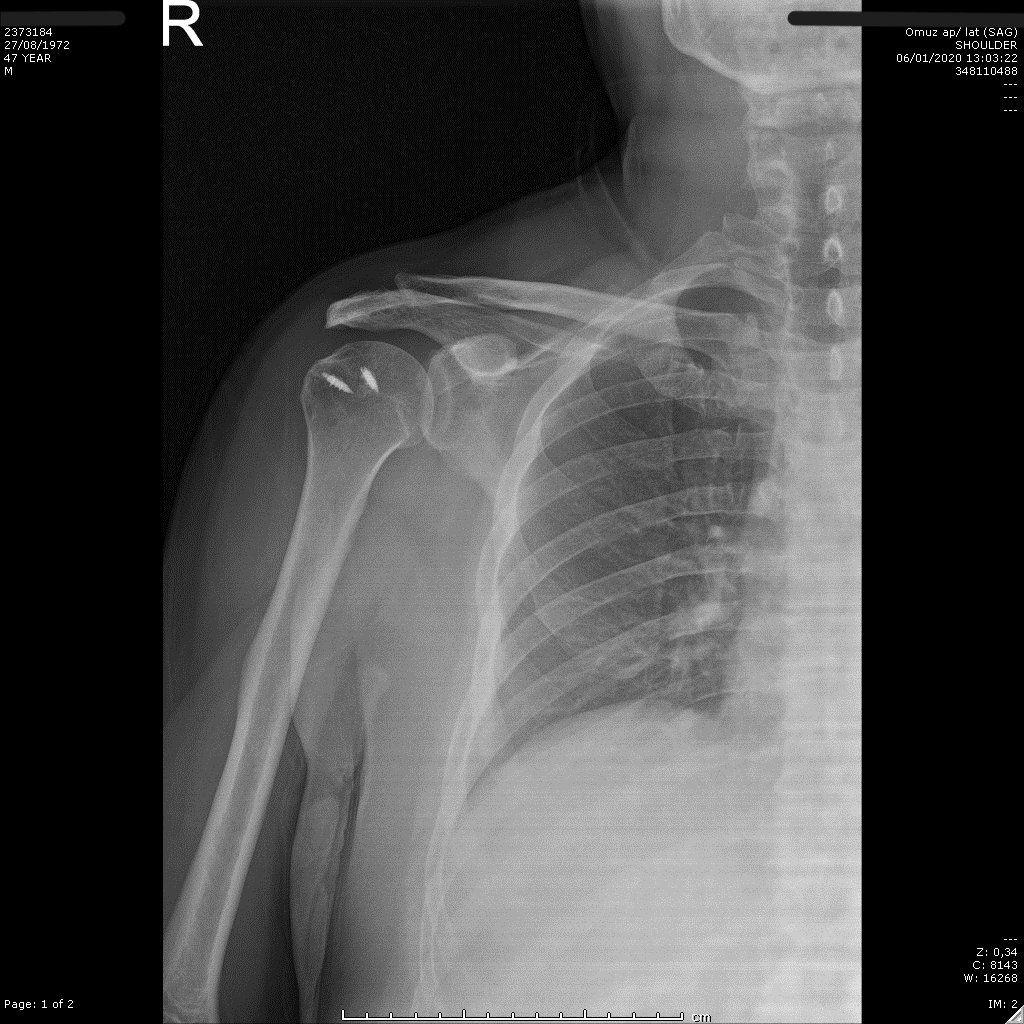

Postoperatif omuz röntgeni — düzelen AHD